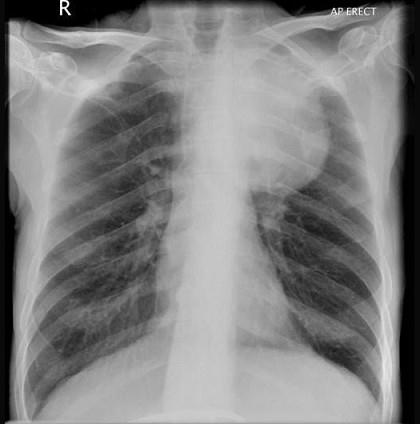

问题 56岁,男,意识错乱情绪不稳定1周,请结合胸片和CT图,选出最可能的诊断 ( )

选项 A.肺癌 B.错构瘤 C.胸内甲状腺肿 D.韦格肉芽肿 E.胸腺瘤

答案 A